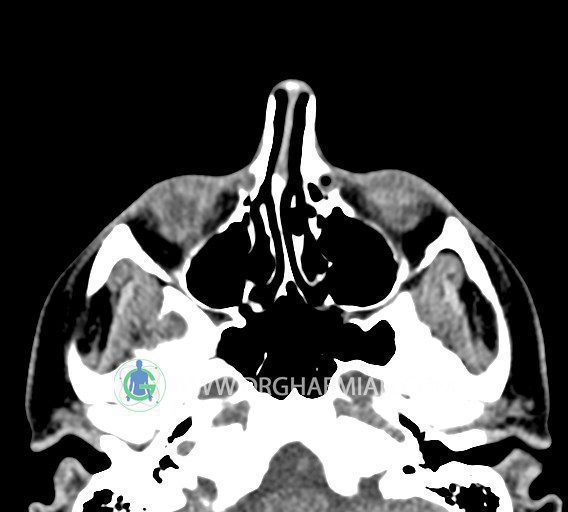

سی تی اسکن سینوس ها یک روش تصویربرداری است که با استفاده از تشعات ایکس تصاویری با جزییات از ناحیه خالی داخل صورت (سینوس ها) ایجاد میکند. در این کیس استئوم فرعی سینوس در دیواره سینوس ماگزیلاری، انحراف سپتوم و کونکا بولوزا مشاهده می شود.

در HRCT اسپيرال از سينوس هاي پارانازال مقاطع کرونال و آگزيال ( 16 اسلايس و مقاطع ظريف 1.5 mm بدون فاصله ، با پنجره استخواني و نسج نرم ) :

– انحراف سپتوم مياني بينی به راست

– کونکا بولوزا در کونکای ميانی چپ و

– اوستيوم فرعي در ديواره مديال سينوس ماگزيلاري راست

مشهود است .